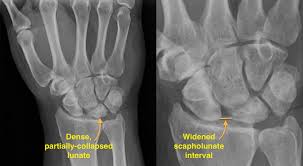

What is Kienböck’s disease?

Avascular necrosis of the lunate bone.

What classification is used for Kienböck’s disease?

Lichtman Stages I–IV (MRI changes → sclerosis → collapse → arthritis).

Radiographic findings in Kienböck’s disease?

Stage I – MRI changes; Stage II – lunate sclerosis; Stage III – collapse ± scaphoid rotation; Stage IV – arthritis.

Treatment options for Kienböck’s disease?

Immobilization, bone grafts, radial shortening/ulnar lengthening, proximal row carpectomy, wrist fusion.